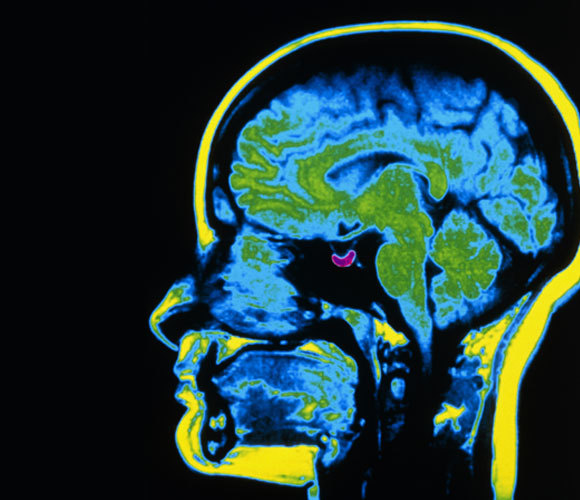

أظهر الباحثون بناءً على فحوصات التّصوير بالرّنين المغناطيسيّ (MRI) أنّ متوسط حجم الغدّة النّخاميّة يتغيّر بدورات سنويّة. تظهر هنا الغدّة النّخاميّة في التّصوير بالرّنين المغناطيسيّ باللون البنفسجيّ البارز |Scott Camazine, Science Source, Science Photo Library

وفقًا للنّموذج، فإنّ عمليّة نموّ وتقلّص الغدد بطيئة وتستمرّ عدّة أشهر، بحيث تمتدّ الدّورة الكاملة سنة تقريبًا. إذا كانت هذه الفرضيّة صحيحة، فيجب أن يتغيّر حجم الغدّة النّخاميّة على مدار السنة. في الواقع، استنادًا على التّصوير بالرّنين المغناطيسيّ، أظهر الباحثون أنّ متوسط حجم الغدّة النّخاميّة يتغيّر بدورات سنويّة- فهي أكبر في الصّيف وأصغر في الشّتاء.